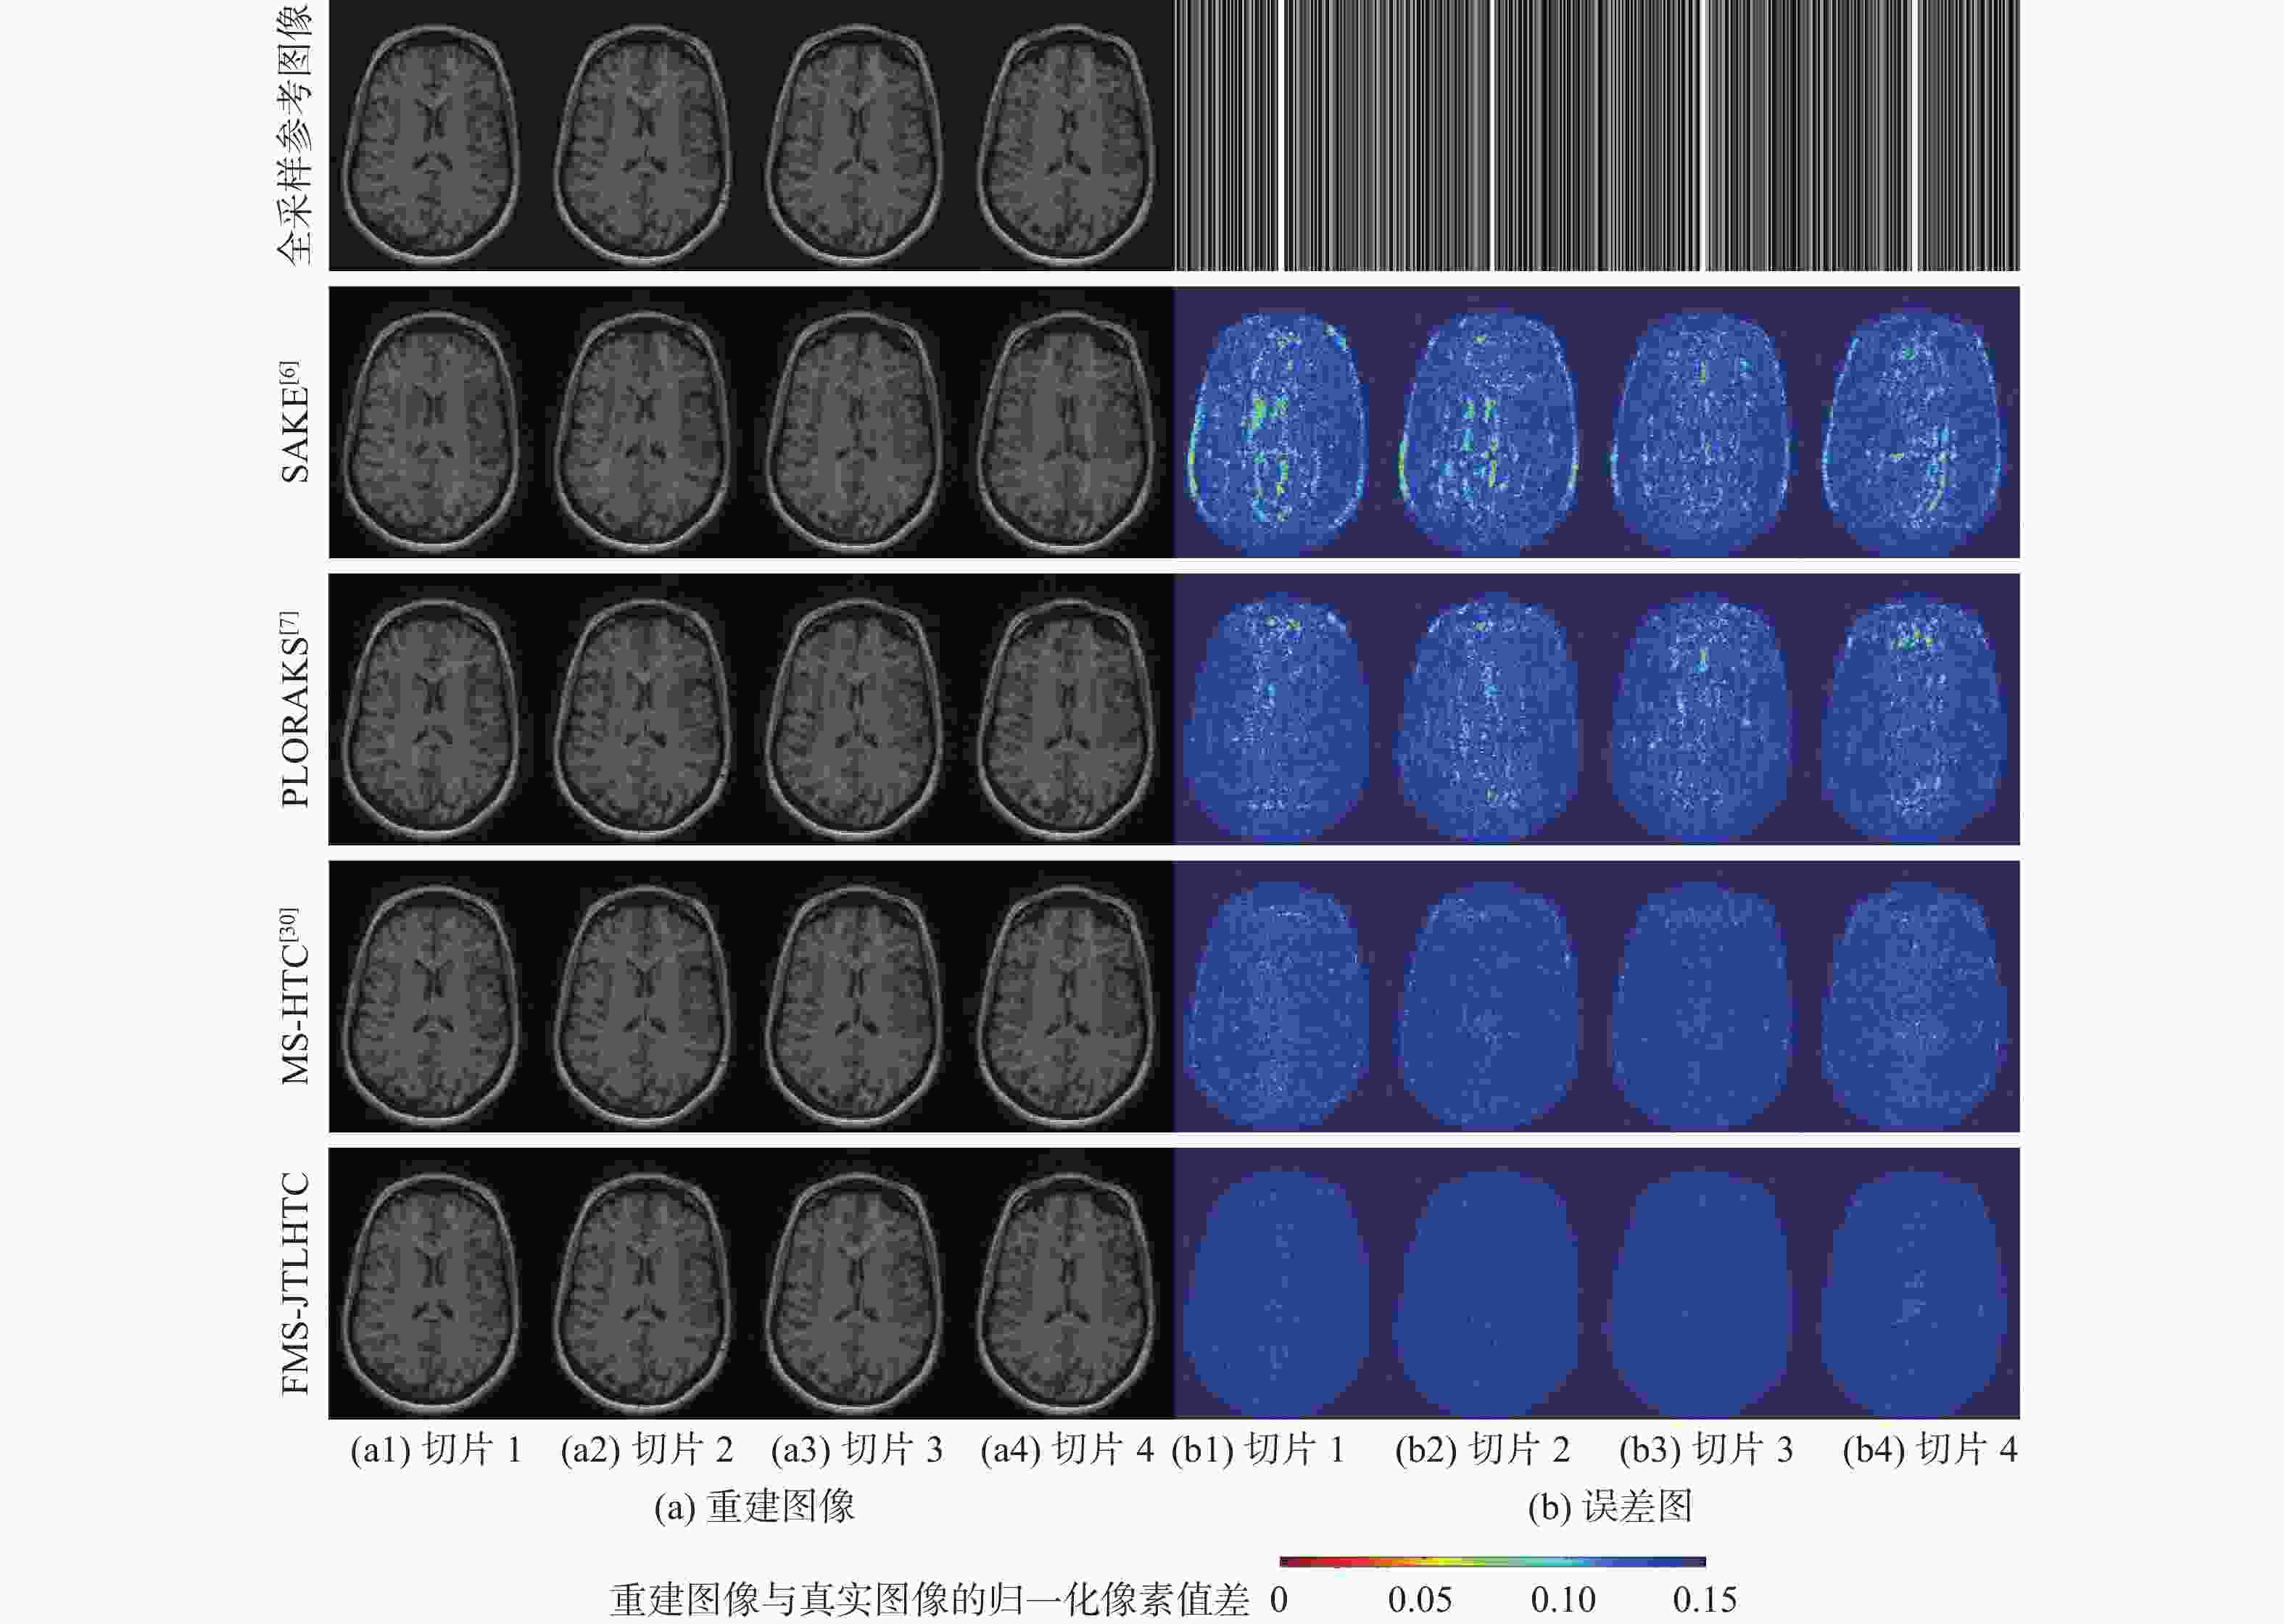

二维(2D)多切片磁共振数据在相邻切片之间具有高度的相关性,通过利用切片间的冗余性能够重建出更高质量的切片图像,但由于硬件条件的限制,2D多切片磁共振成像(MRI)需要耗费大量时间。为提高2D多切片磁共振图像的重建质量和重建速度,将联合稀疏变换学习正则项引入到多切片Hankel张量完成(MS-HTC)模型中,提出一种快速2D多切片磁共振成像重建(FMS-JTLHTC)算法。该算法使用交替方向乘子法对目标问题进行求解;引入快速迭代收缩阈值法加快收敛,并使用图形处理器对算法进行加速。使用4组脑部数据集在2种不同采样模式下进行实验,结果表明:FMS-JTLHTC算法的峰值信噪比(PSNR)相较于同时自动校准和K空间估计(SAKE)算法、并行成像数据的局部K空间领域的低秩建模(PLORAKS)算法和MS-HTC算法分别平均提高了4.04 dB、3.67 dB和2.07 dB,而且重建速度相比MS-HTC算法提高了14倍。

Abstract:Due to the significant correlation between neighboring slices in two-dimensional (2D) multi-slice magnetic resonance data, higher quality slice pictures can be reconstructed by taking use of the redundancy between slices. However, 2D multi-slice magnetic resonance imaging requires an amount of time. To improve the reconstruction quality and speed of 2D multi-slice (MRI) images, proposes a fast 2D multi-slice MRI reconstruction (FMS-JTLHTC) algorithm, which introduces the joint transform learning regular term into the multi-slice hankel tensor completion (MS-HTC) model. Prior to introducing the fast iterative shrinkage-thresholding procedure to accelerate convergence and utilize the graphics processing unit to speed up the procedure, the alternating direction method of multipliers is used to solve the objective issue. Experiments using four brain datasets in two different sampling modes show that the peak signal-to-noise ratio (PSNR) of the FMS-JTLHTC algorithm is improved by an average of 4.04 dB, 3.67 dB, and 2.07 dB compared to the simultaneous atuo-calibrating and K-space estimation (SAKE), low-rank modeling of local K-space neighborhoods with parallel imaging data (PLORAKS) and MS-HTC algorithms, respectively, the reconstruction speed is improved by a factor of 14 compared to the MS-HTC algorithm.